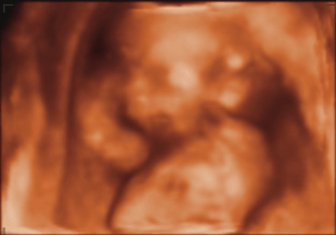

Et voila sa bouille :)

• bébé 16 sa 6.png

bébé 16 sa 6.png

28.4 KB · Affichages: 68